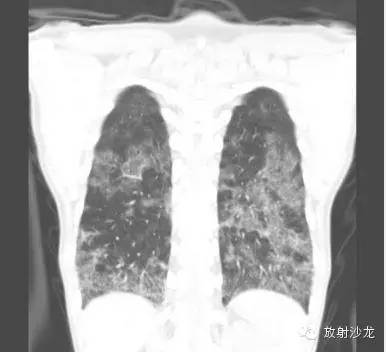

首次就诊CT:

胸片示两肺中下野边界不清的磨玻璃样阴影(GGO)。CT示两肺地图样分布的GGO,主要位于两肺上叶、右肺中叶及两肺下叶,其中两肺下叶多发的GGO融合并伴有小叶间隔增厚。2周后随访胸片示双肺野弥漫分布的GGO增多。患者第一次就诊时未告知自己的性取向。只告知了曾接触过染发剂。患者按肺间质性疾病给予激素治疗。然而,治疗后患者的症状和影像学表现均加重。患者血液检测结果显示艾滋病病毒阳性。支气管肺泡灌洗液GMS染色示大量的卡氏肺孢子虫。